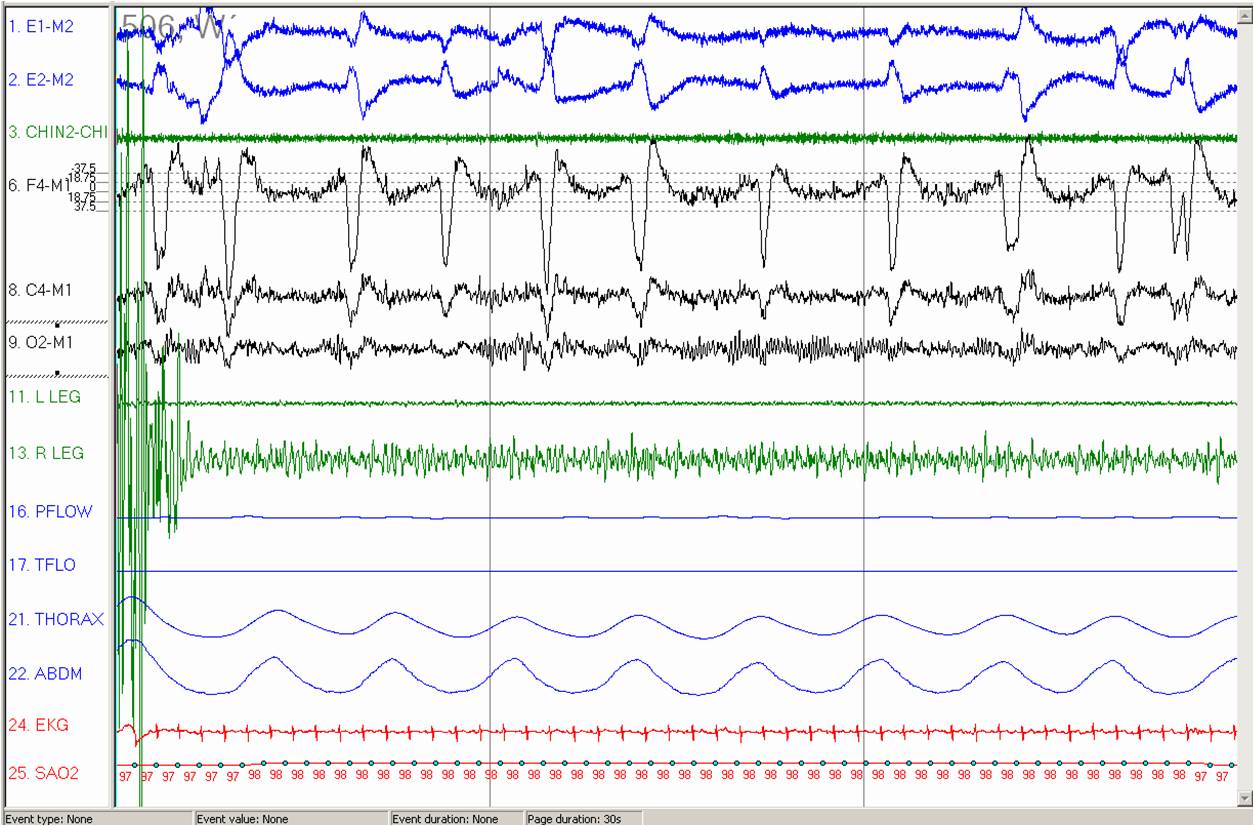

In the 30 second epoch presented, what is the artifact noted in the F4 EEG lead?

note: chin lead malfunctioning so not included)

Blink Artifact

–The artifact is a blink artifact. Note that the artifacts correlate with the rapid eye movement activity seen in the E1 and E2 leads.

–The patient is awake as evidenced by the alpha rhythm seen in the O2 EEG lead. Given the patient is awake, the frequent rapid eye movements indicate blinking.

–As the F4 lead is positioned above the eye, eye movements can occasionally be recorded in this lead, leading to the artifact seen in this fragment.

–Usually, blink artifact is not recorded in the central and occipital leads as they are located too far away from the electrical activity to record it. However, in this particular fragment, some artifact can also be seen in the C4 lead.

Images Legend:

–E1-M2 and E2-M2, left and respectively right outer cantus electro-oculography electrodes; chin2-chin 1, submental electromyography signal; F4-M1, C4-M1 and O2-M1, right frontal, central and respectively, occipital electroencephalography electrodes; L LEG and R LEG, left and respectively right lower limbs electromyography electrodes; PFLOW, nasal pressure signal; TFLO, the airflow via nasal/oral thermocouples; THORAX and ABDM, chest and respectively abdominal walls motion via inductive plethysmography; EKG, one standard electrocardiogram lead; SAO2, the pulse oximetry by finger probe.